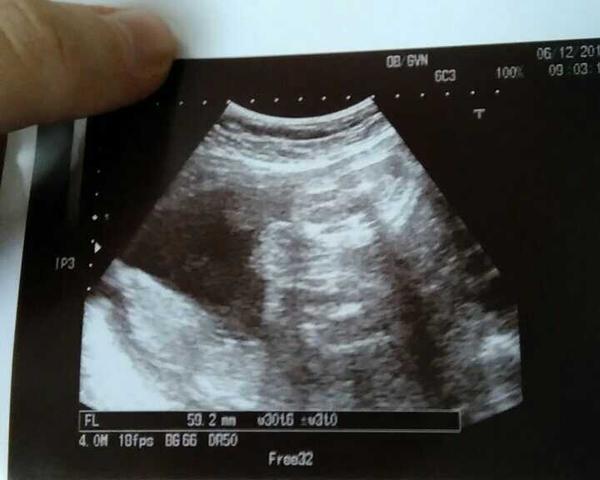

Je to holčička nebo chlapeček? Foto ultrazvuku

Ahoj maminky a budoucí maminky 😉 Prosím, poradila byste mi některá, co vidíte na fotce z ultrazvuku ve 20. týdnu za pohlaví? Určitě jste foteček viděly už mraky, proto vás žádám o radu...Nechci nikoho ovlivnit, proto svůj tip řeknu později 🙂 Děkuju moc!!!

@nikyta159: no ja sem toho zdarny priklad :D do 23tt kluk pak uz jen holka a mam ji :-* doufam ze se ted nesekla !!! @mariejosef: podle me jasna holka 🙂

@mariejosef podle mě taky jasná holka, ale nejsem doktor...jsem fakt zvědavá, co se v ti v.tom bříšku skrývá.. 🙂